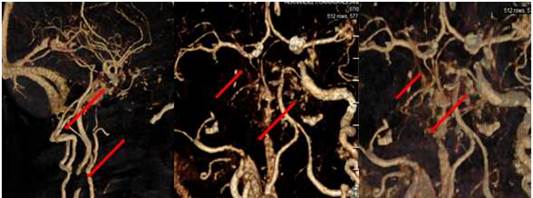

Angio-TC de cráneo (Figura 2): Destaca la presencia de oclusión completa de la arteria carótida interna derecha en su origen, con demostración de flujo de contraste a nivel de la arteria carótida interna en regiones petrosa, cavernosa y ACM, con una ACP derecha que nace directamente de la carótida supraclinoidea, la misma se encuentra ocluida en su tercio distal. No signos de disección. Arterias carótida izquierda y vertebrales permeables sin hallazgos.

Hablamos de un varón de 68 años de edad, hipertenso, diabético y con dislipidemia, que debuta con un cuadro clínico de hemiparesia izquierda, apraxia cinética y hemianopsia homónima; focalidad neurológica que habitualmente corresponde y es atribuida a territorio vascular de la ACM del hemisferio derecho, asociado con una ausencia de flujo en la carótida interna proximal homónima evidenciada en el Doppler. Estos hallazgos sugieren plantear con mucha fuerza en sus inicios, un infarto en el territorio de la ACM derecha. Sin embargo, los estudios posteriores (TAC de cráneo a las 48 h de evolución) (Figura 1) imponen reconsiderar el diagnóstico y valorar la posibilidad de variantes anatómicas en la circulación intracraneal, comprobando estos últimos con el estudio de Angio-TC (Figura 2).